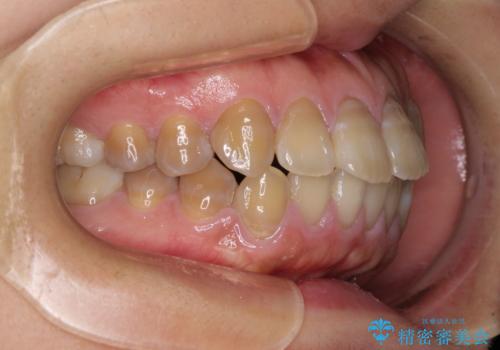

4本の歯を抜歯したことで、飛び出していた口元が引っ込み、横顔が大きく改善されました。

上下前歯が著しく前突している状態であったので、上下左右の第1小臼歯4本を抜歯し、ワイヤー装置にて矯正治療を行うこととしました。